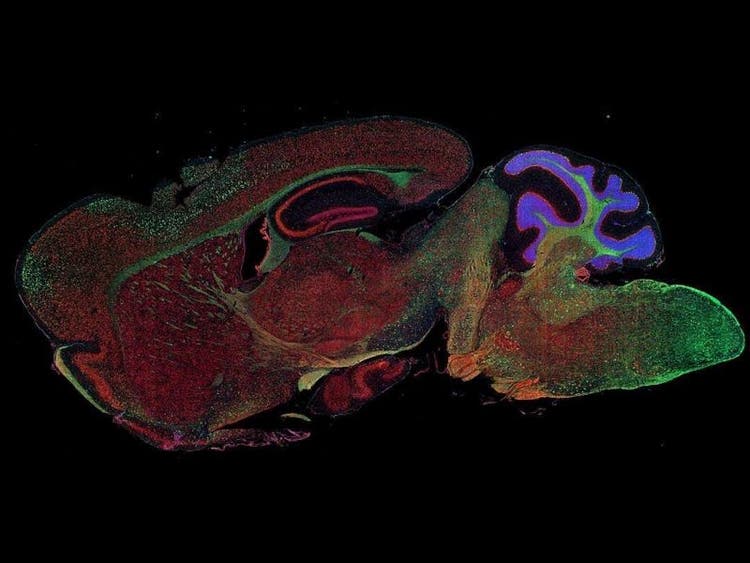

Fluorescence imaging of a mouse brain

While each of these images looks distinct up close, they all come together to form one view of a mouse brain captured with fluorescence imaging.

British scientist Sir George G. Stokes first observed that the mineral fluorspar exhibits fluorescence when illuminated with ultraviolet light, and he coined the word ‘fluorescence’. Stokes noticed that the fluorescing light has longer wavelengths than the excitation light, a phenomenon now known as the Stokes shift. Fluorescence microscopy is an excellent method to study material that can fluoresce either in its natural form (termed primary or autofluorescence) or when treated with chemicals that can fluoresce (known as secondary fluorescence).